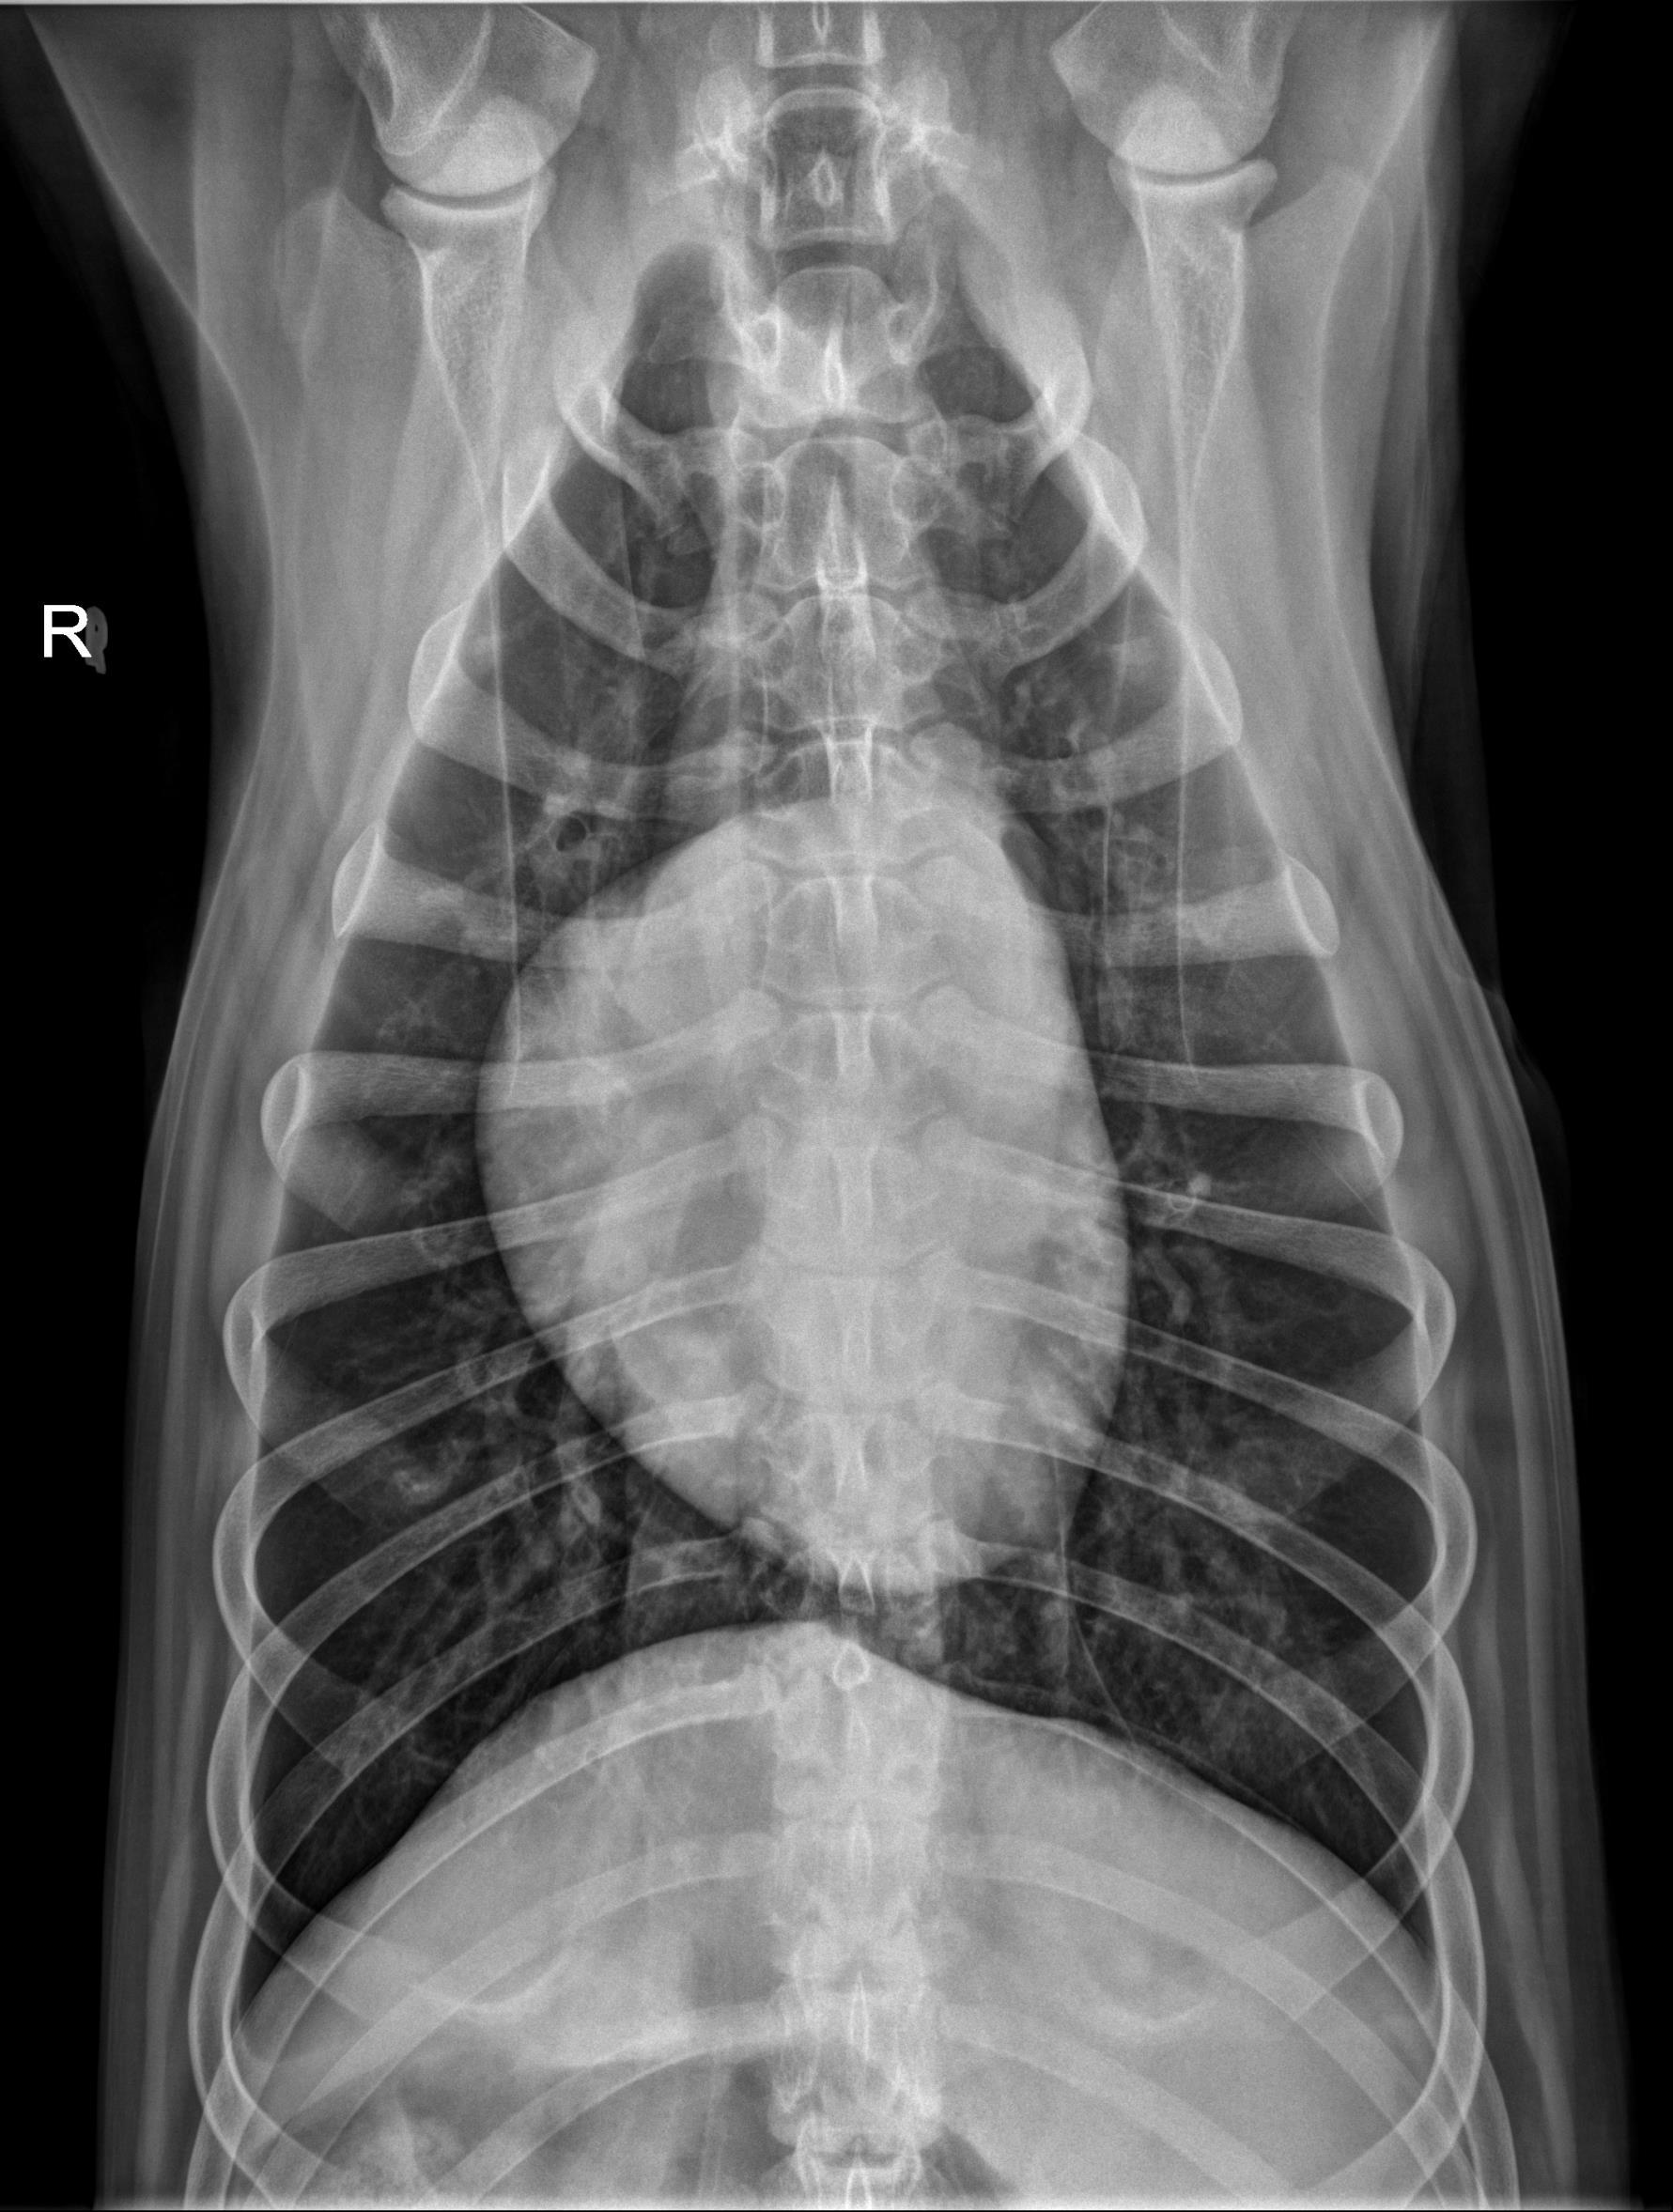

Thorax ventrodorsal and lateral radiographs are available for interpretation.

Thorax: The pulmonary parenchyma is normal. The cardiac silhouette and pulmonary vessels are normal. The pleural and mediastinal spaces are normal.

There is mild to moderate osteolysis of the caudal endplate of T9 and the cranial endplate of T10 which is surrounded by sclerotic bone. The T9-10 intervertebral disc space is narrowed.

The appearance of the T9-10 intervertebral disc space is most concerning for discospondylitis.